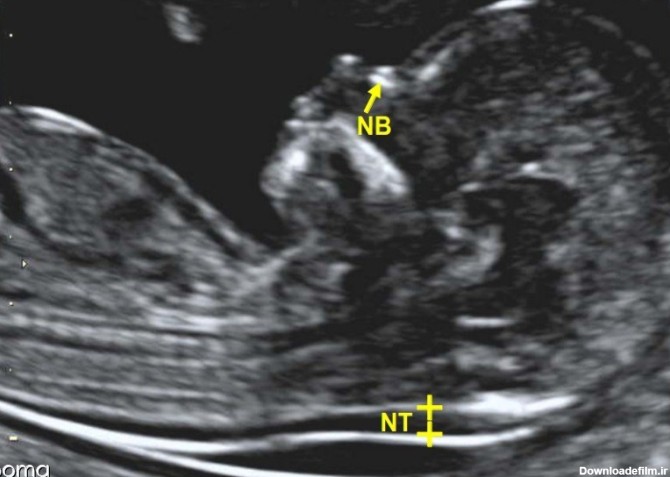

سونوگرافی NT مخفف nuchal-translucency به معنای فضای شفاف پشت گردن است و احتمال بروز نقایص کروموزومی را پیش بینی می کند. تمام جنین ها پشت گردنشان مایع دارند

کاربرد سونوگرافی NT - برای تشخیص برخی از ناهنجاری های مادرزادی مانند سندرم داون، ناهنجاری های کروموزومی و مشکلات قلبی مادرزادی، از این نوع سونوگرافی ...